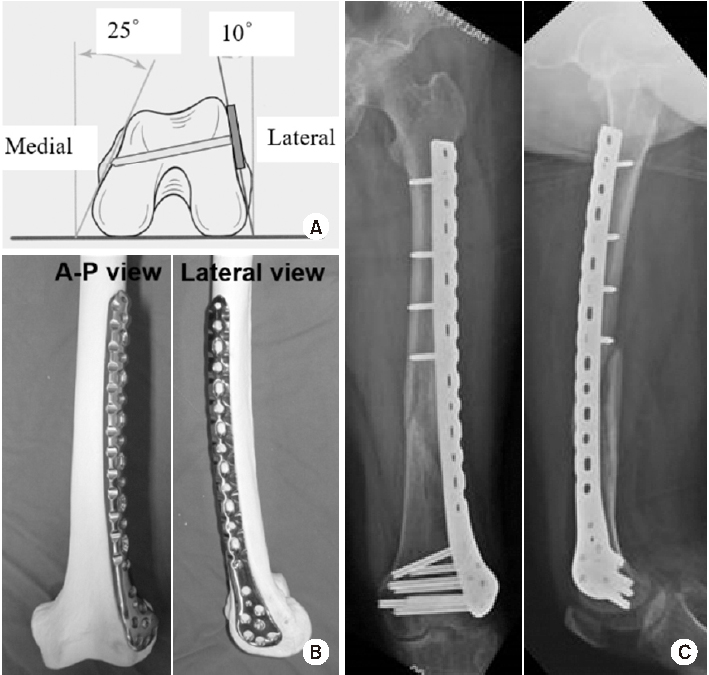

Fig. 5

(A) Schematic diagram showing the axial shape of the distal femur and the appropriate length of distal locking screw. (B) Anteroposterior (A–P) and lateral photos showing the appropriate position of the lateral anatomical locking plate in the distal femur model. (C) A–P and lateral radiographs showing the appropriate position of the locking plate fixed in a distal femur fracture of a 72-year-old female patient.